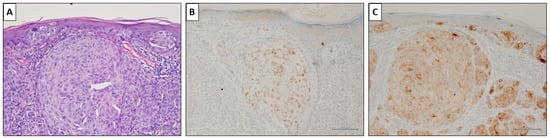

3.2. PRAME Immunohistochemistry and Diagnostic Performance